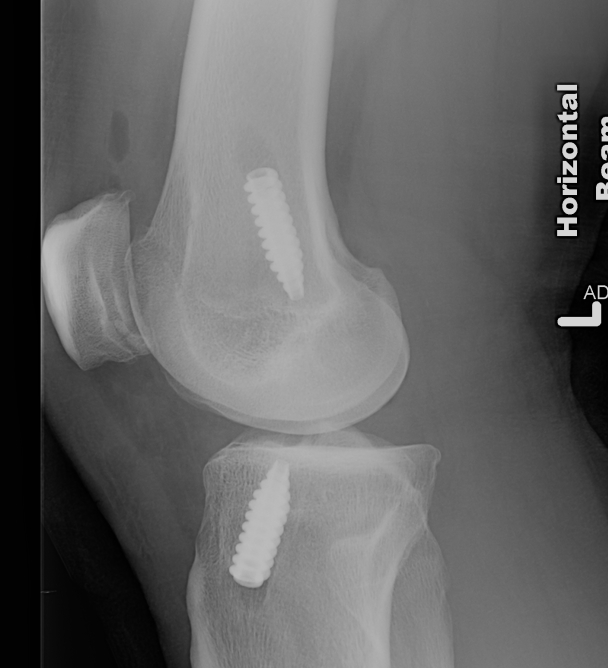

Ream tibial and femoral tunnels

- line to line to graft size

- outside in to preserve native ACL

Pass graft

- measure tibial tunnel

- apply artery forcep at appropriate distance from central graft

- allows you to know when graft is pulled through enough

- the LARS has a specifice portion designed to be inside the native ACL

- pass from the tibia up through the knee into the femur

Secure

- insert femoral screw outside in

- tension tibial side

- must not overtension as there is no give in the graft

- secure tibial side with screw